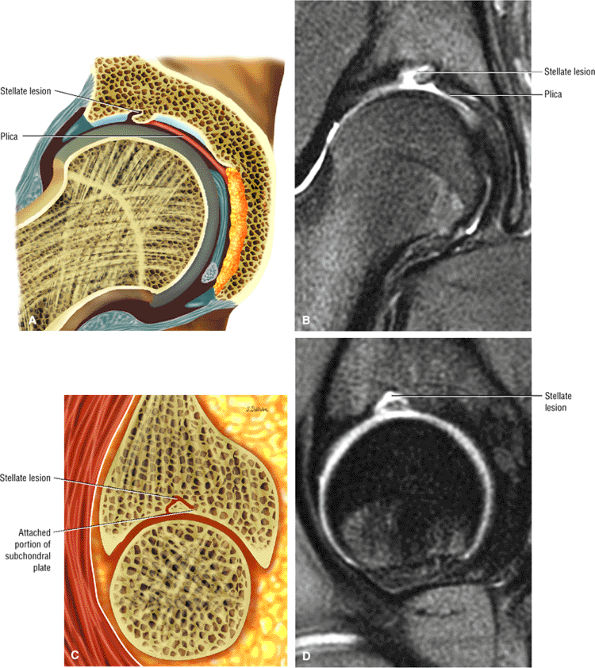

The stellate lesion or crease represents a normal bare area superior to the acetabular fossa.

An enlarged or hypertrophied labrum may occur in patients with mild DDH.17 We have observed a femoral head chondral crease (Fig. 3.66) in these patients, creating a demarcation trough medial to a femoral head bump immediately proximal to the physeal scar. Patients who demonstrate femoroacetabular impingement (or lateral acetabular rim syndrome in DDH) also have direct impingement between the lateral acetabular labrum and the femoral head.

FIGURE 3.66 ● Femoral head chondral crease with adjacent bump proximal to the physis in a mild DDH case with a hypertrophied labrum. (A) A mild crease is shown on this coronal FS PD FSE image. (B) This coronal FS PD FSE image shows a prominent femoral head crease secondary to impingement between the hypertrophied labrum and the articular surface of the lateral femoral head proximal to the physeal scar in another DDH patient. (C) Arthroscopic view of femoral head crease demarcating the femoral head articular cartilage medially from the lateral bump. The crease or cleft is opposite the lateral edge of the hypertrophied labrum. The normal perilabral sulcus is also shown between the labrum and capsule.